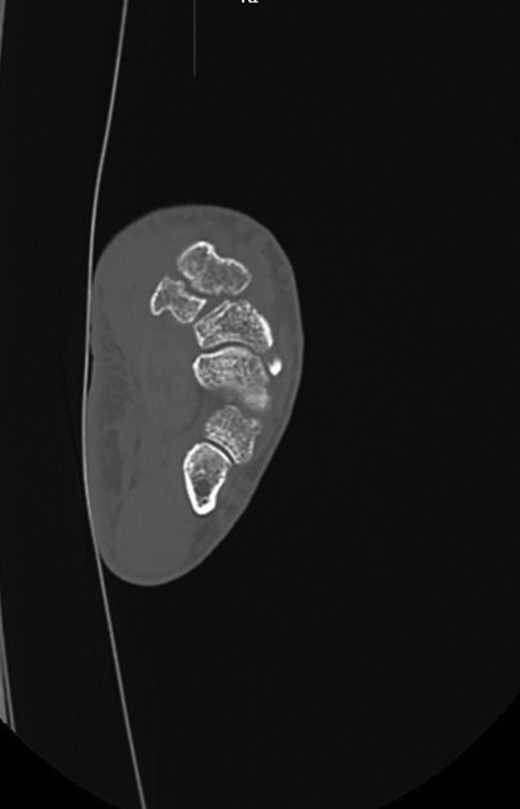

The CT scan (Fig. 2) showed a coronal fracture of the trapezium which was not united. At this stage the symptoms of pain and instability continued to persist and were preventing him returning to mountain biking. As the imaging also showed that there were no degenerative changes in either the trapezio-metacarpal joint or the scapho-trapezial joint, the decision was made to proceed with debridement of the non-union and rigid internal fixation.

The trapezium was exposed through a Wagner approach. Intra-operatively a coronal split of the trapezium was found with no evidence of union. The fracture site was debrided, reduced and fixed with two headless compression screws. The thumb was immobilized in a plaster following surgery. Six weeks following surgery plaster was removed and the patient started physiotherapy to regain range of movement and strength. His plain radiographs at this point showed progression to union.